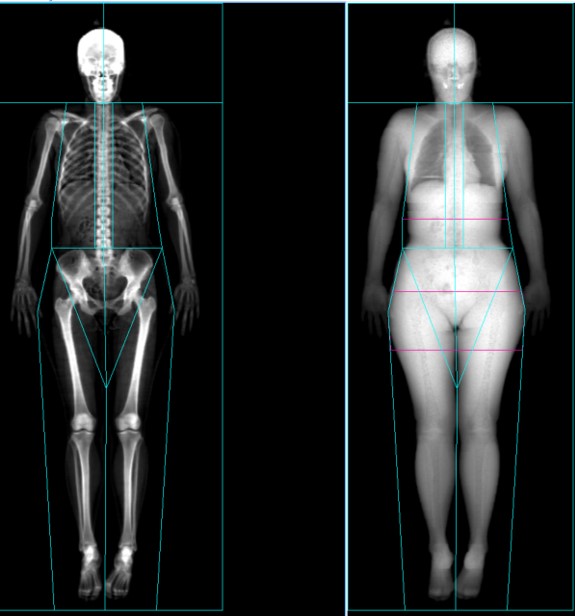

DXA法における体組成計測は、X線の吸収を利用して体内の脂肪量、非脂肪量、骨量の3つの計測を行います。

計測領域に関わる用語

測定対象となる関心領域(ROI)です。GEヘルスケア社のDXA装置の場合、最大で22の領域別での結果をみることができます。

アンドロイド

腹部にある関心領域です。

アンドロイドROIの高さは、坐骨頂カットラインから、頭部~坐骨頂カットラインまでの長さの20%上方となります。

被検者の体格を考慮した形でROI設定を行います。

ガイノイド

臀部領域にある関心領域です。

ガイノイドROIの高さは、アンドロイドROIの高さの2倍です。 ROI上縁の位置は、坐骨頂ラインから、アンドロイドROIの高さの1.5倍の下方に位置します。